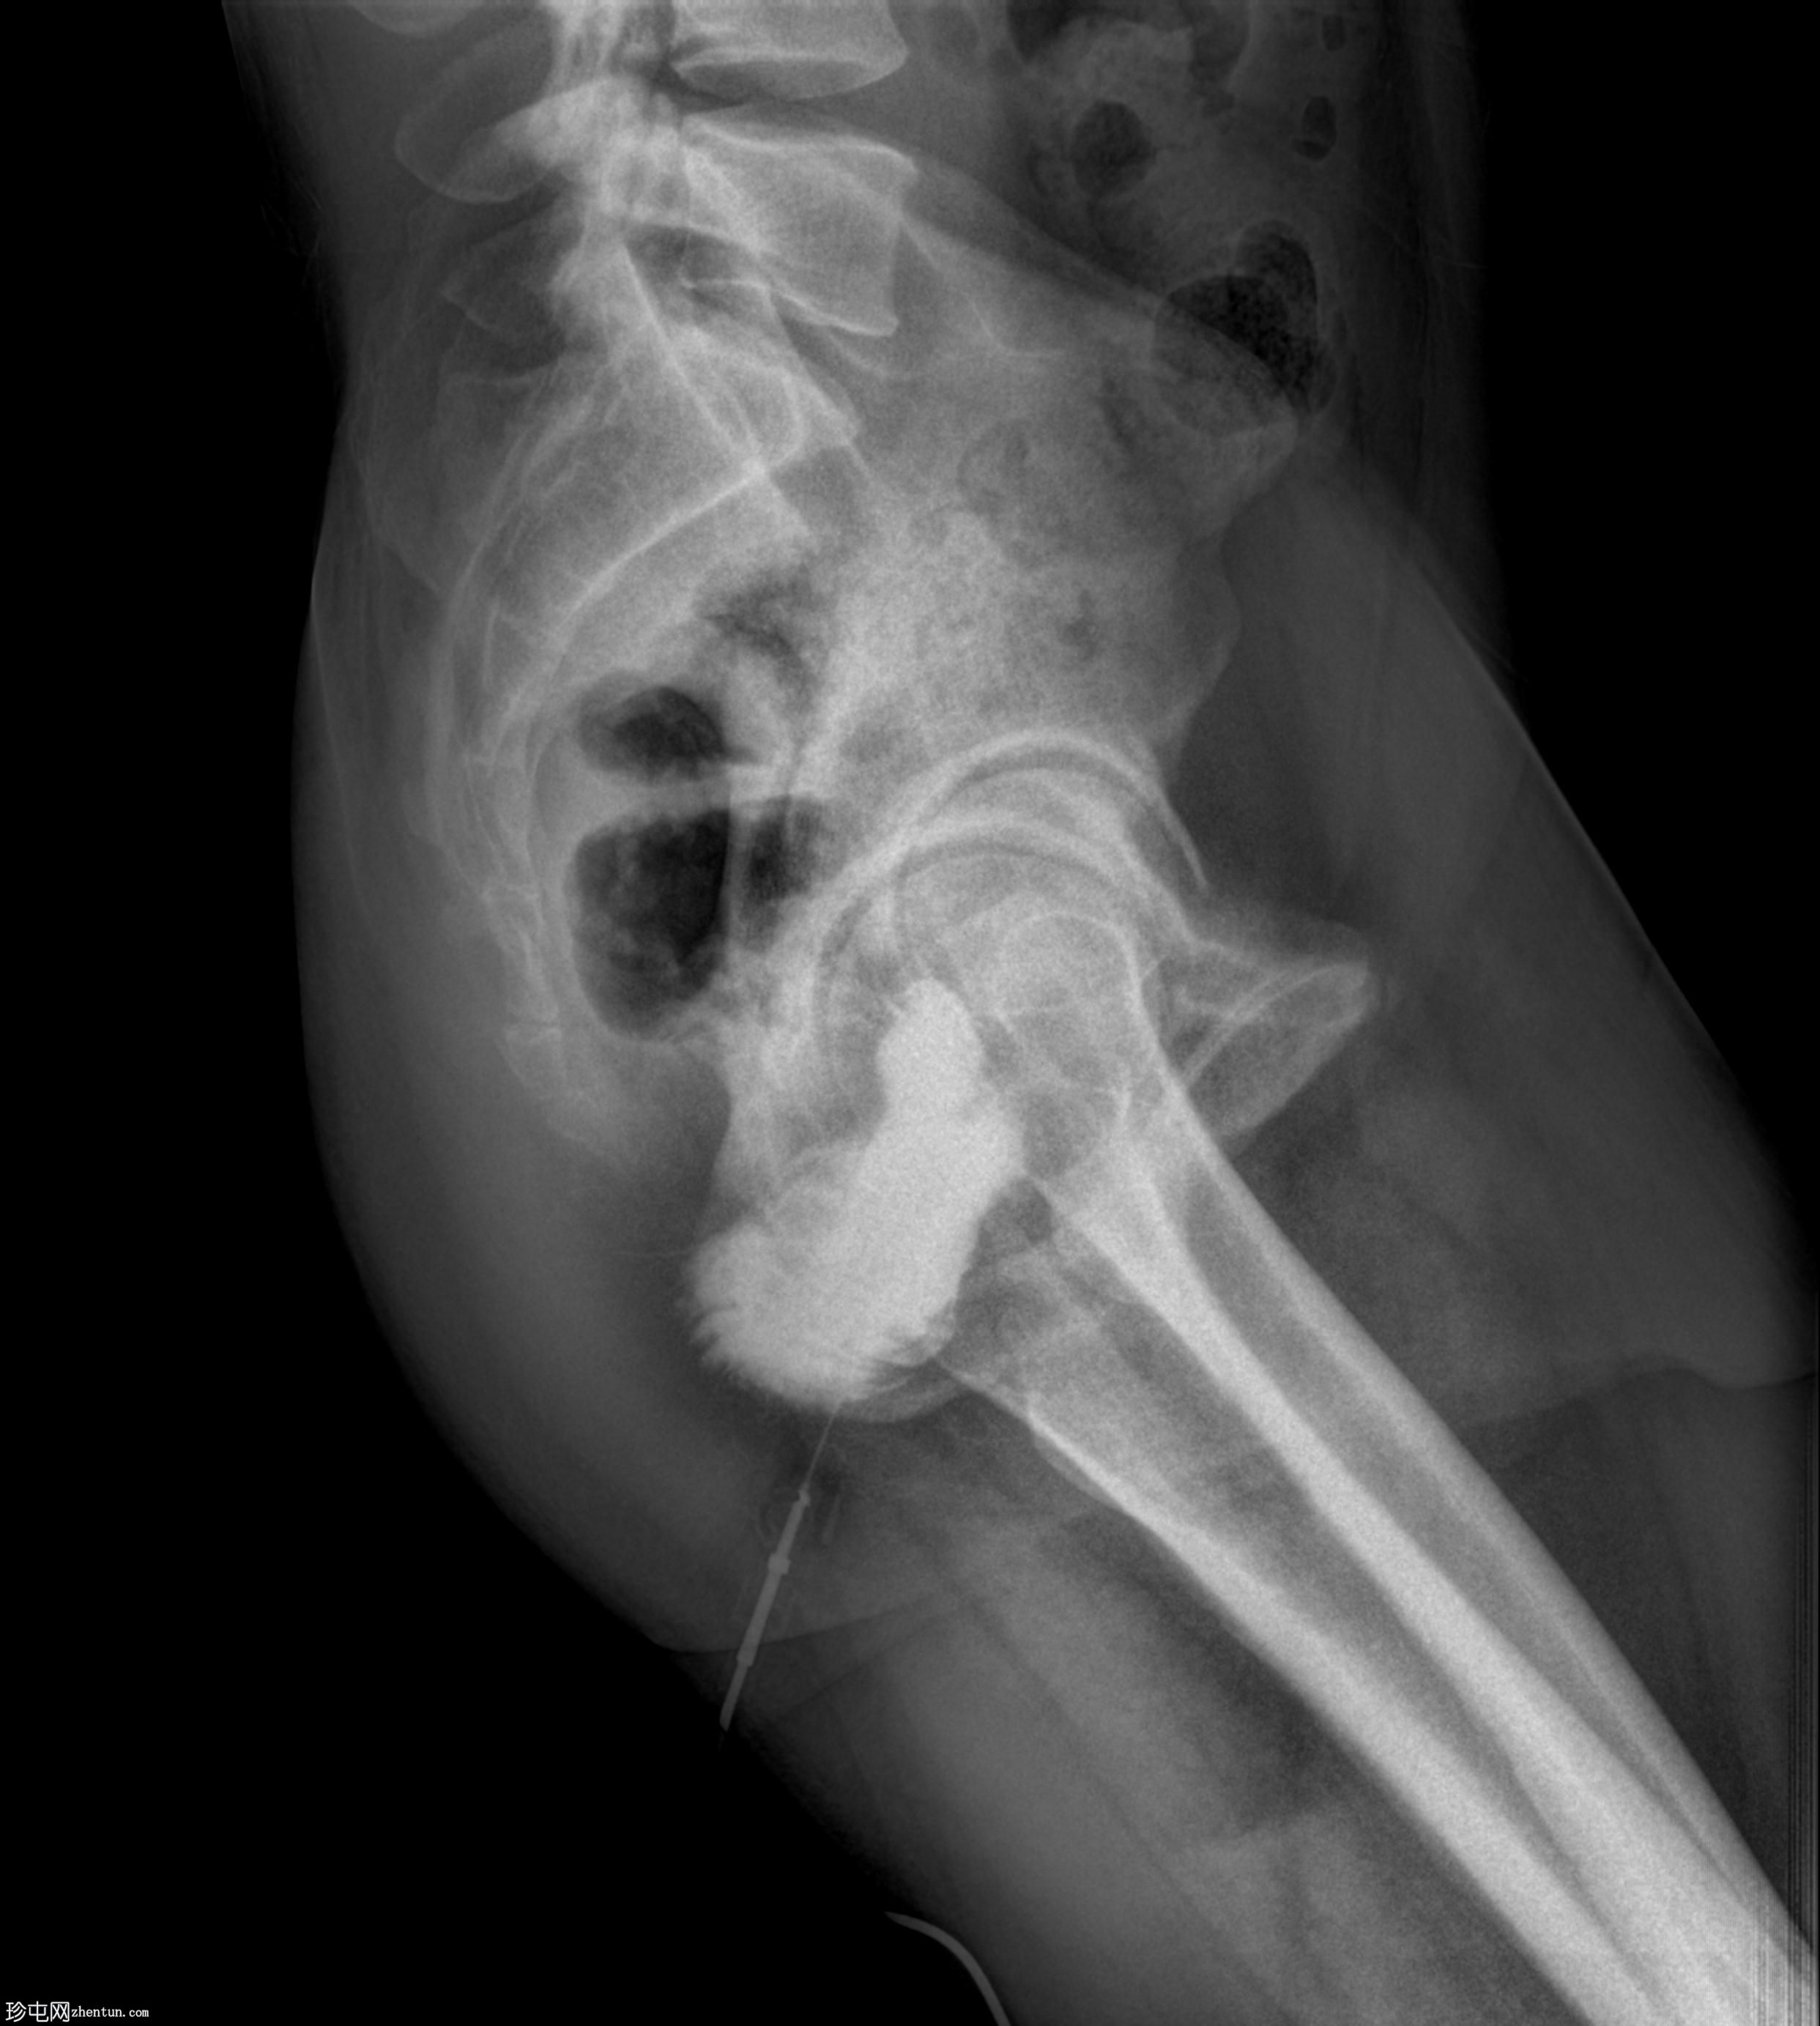

矢状位

经脓性分泌物开口注入造影剂,显示右侧肛周脓肿显影。

未见造影剂明显外渗至肛管或直肠。

透视瘘管造影图像显示右侧肛周脓肿较大,与肛管或直肠无交通。